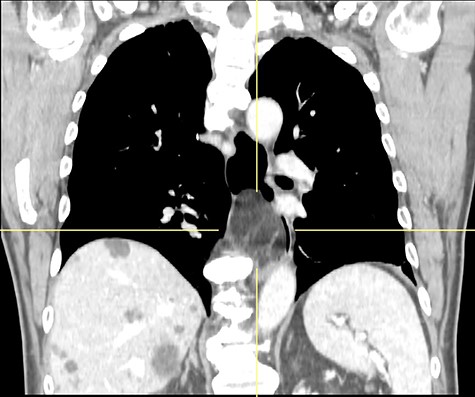

A 77-year-old man was referred for a long history of heartburn and more recent onset of progressive regurgitation, dysphagia and weight loss. Empirical therapy with proton-pump inhibitors was ineffective. The gastroesophageal reflux disease health-related quality of life (GERD-HRQL) score was 22. The functional outcome swallowing scale (FOSS) score for dysphagia was 2. Physical examination was unremarkable. Upper gastrointestinal endoscopy showed a soft submucosal bulging in the posterior wall of the distal esophagus located between 29 and 39 cm from the incisors, and 3 cm proximal to the esophago-gastric junction (Fig. 1). Computed tomography of chest and abdomen showed a fat-density submucosal mass with luminal narrowing (Fig. 2). High resolution manometry (HRM) showed pan-esophageal pressurization in 100% of the swallows and a resting lower esophageal sphincter (LES) pressure of 11.2 mmHg (Fig. 3). Through a laparoscopic transhiatal approach, esophageal myotomy, mass enucleation, suture approximation of the muscle layer, posterior cruroplasty, and 270° Toupet fundoplication was performed (Fig. 4). The procedure took 55 min. Postoperative course was uneventful. A gastrographin swallow study on Day 1 showed a normal esophagogastric transit and the absence of leaks. The patient was discharged home on postoperative Day 2. Pathology confirmed the clinical suspicion of esophageal lipoma (Fig. 5). High-resolution manometry was repeated at the 6 month follow-up and showed an ineffective esophageal motility, with 50% of non-conducted swallows. The resting LES pressure increased (17.4 mmHg), and the swallow-induced LES relaxation was normal. The GERD-HRQL score was 3 and the FOSS score was 0.

CT scan showing fat-density submucosal mass with luminal narrowing.